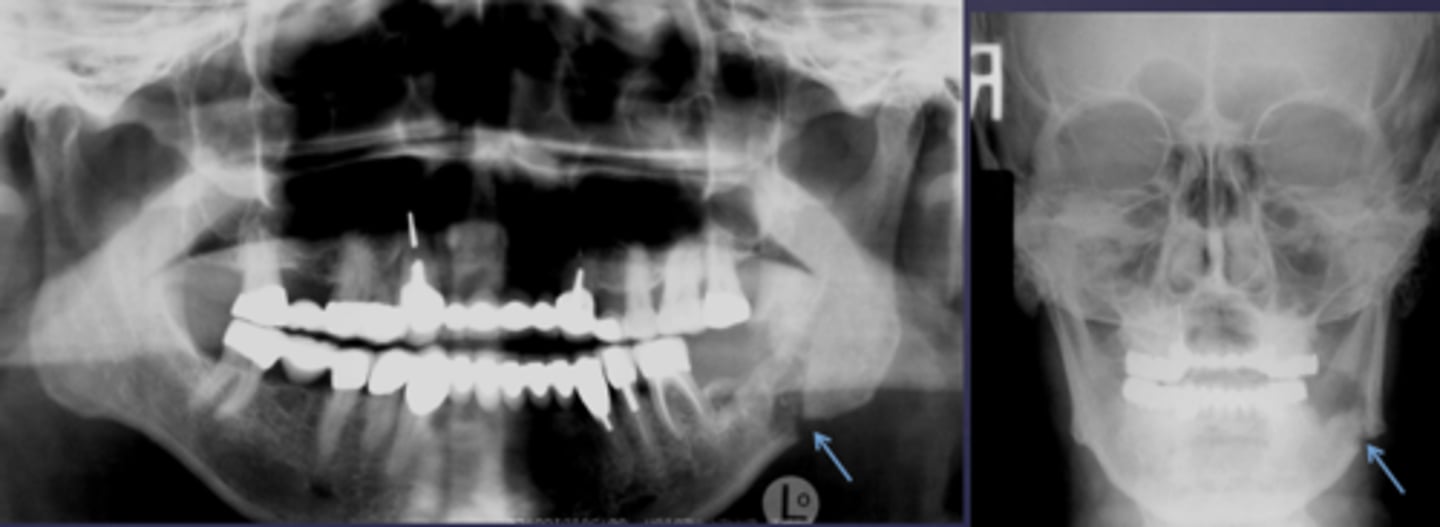

What is the differential diagnosis of the left angle-ramus of mandible?

diffuse sclerosing osteomyelitis (chronic osteomyelitis)

A patient's pano is shown and presents with wrist symptoms. What is the differential diagnosis?

SAPHO Syndrome